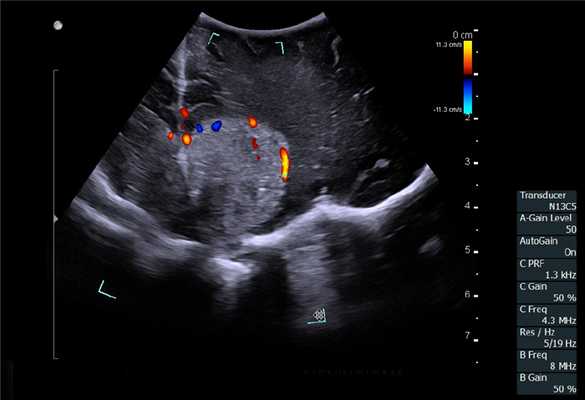

В случае выявления образований в печени и измененных забрюшинных лимфатических узлов (при необходимости) выполняли пункционно-аспирационную биопсию. При этом образование, эхографически подозрительное на метастатический узел, располагалось по центру сканирующей поверхности датчика и тем самым по центру монитора. При исследовании обязательно использовали методику допплерографии для выбора участков с наименьшим кровоснабжением. Эта же методика позволяла визуализировать кровеносные сосуды над узловым образованием и избежать их повреждения. После выполнения указанных моментов выполняли непосредственно пункцию.

Особенностью проведения интраоперационного ультразвукового исследования у пациентов с первичным поражением печени является то, что гепатоцеллюлярный рак часто развивается на фоне цирроза печени. Следовательно, если опухоль локализуется в толще паренхимы, а так же имеет не большие размеры, пальпаторно определить ее границы крайне затруднительно. Таким образом, задачи установленные перед интраоперационной ультразвуковой томографией были несколько иными, а именно: определение границ опухоли, разметка зоны резекции, определение связи с магистральными сосудами (рис. 2 а,б).

Рис. 2. Метастатические очаги (стрелки) в печени на фоне цирроза.